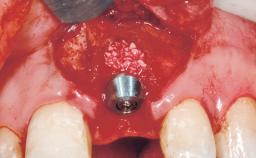

Late Placement of an Implant in a Maxillary Left Central Incisor Site

A 36-year-old female patient was referred for the replacement of the upper left central incisor (tooth 21), which had fractured. Although the tooth had been asymptomatic for many years, the crown began to loosen, at which time she presented to her dentist for an assessment. Teeth 21 and 22 had both been endodontically treated many years previously. She was a healthy individual and a non-smoker.

Type of Implants Two-Piece

Attachment Two-Piece

Placement Protocol Early or late implant placement

Bone Volume Deficient horizontally, requiring prior grafting